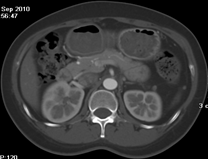

目前臨床對于16層CT的認可主要集中在三維成像領域上的突破.在16層CT的產品平臺上,常規(guī)掃描就能實現(xiàn)滿足三維成像的要求,因此16層也被稱為三維CT,三維成像給臨床診斷帶來了更精確更豐富的診斷信息,我們以臨床為例:

如上圖所示,相鄰的三張軸位圖像未見明顯異常,根據(jù)傳統(tǒng)軸位圖像很難得到準確的臨床診斷。

同一病人利用容積數(shù)據(jù)進行三維處理后,高品質MPR和三維圖像上則清晰顯示了縱向排列的腹腔干與腸系膜上動脈相鄰近,血管發(fā)生變 異,近端血管閉塞,為臨床提供了精確的診斷信息。